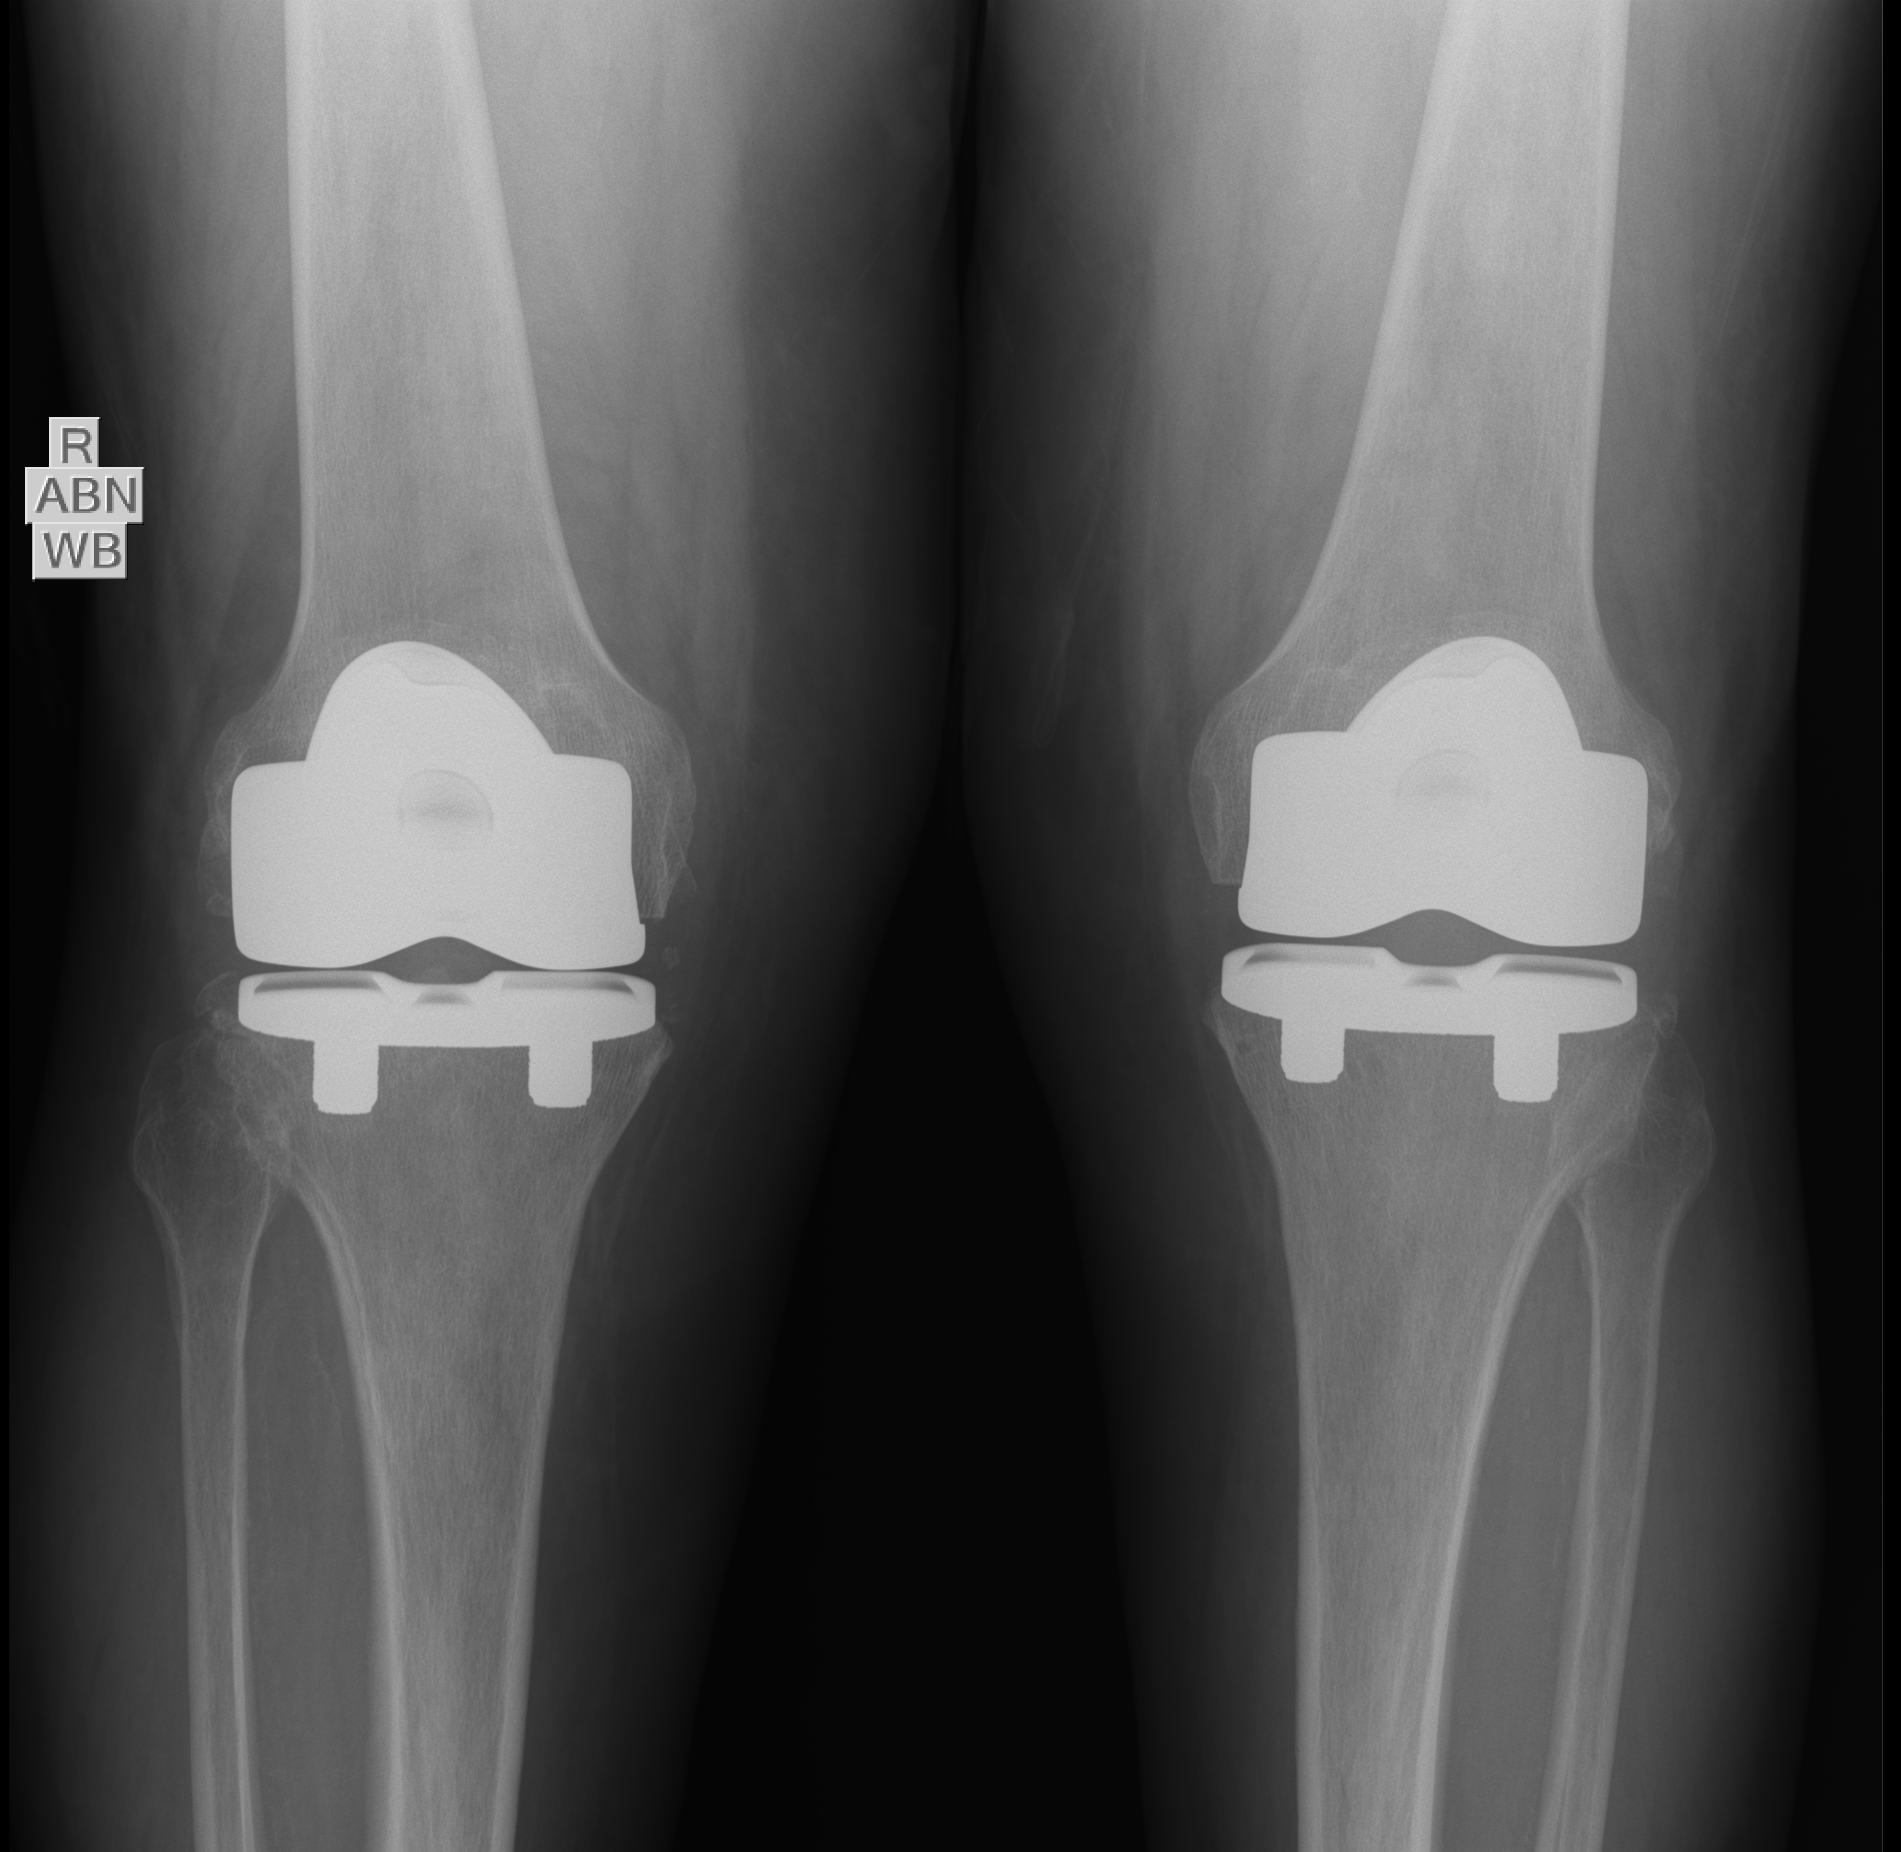

Total Knee Replacement:

What is a Knee Replacement?

A knee replacement or “total knee arthroplasty” is a surgical procedure designed to replace a worn out knee joint. Most knee replacements are made up of 3 or 4 main parts.

Femur: a curved metal cap is fit to the bottom part of the femur.

Tibia: a flat metal baseplate is fit to the the top part of the tibia.

Liner: a liner made of a special plastic (ultra high molecular weight polyethylene) snaps onto the to replace your cartilage.

Patella: a button made of a special plastic (ultra high molecular weight polyethylene) is sometimes used to resurface the kneecap (patella).

A knee replacement is typically performed using an incision over the midline of the knee. Different measuring devices, jigs and even robotic instruments are used to precisely align the components to ensure an appropriate fit and alignment of the components. These components are then either cemented or press fit in place depending on each patients bone quality and deformity.